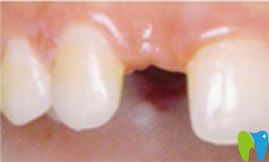

說(shuō)起我來(lái)龍巖萬(wàn)翔口腔種植牙齒的原因真是無(wú)比憂傷,一次醉酒后不小心摔倒了,門牙磕掉了一個(gè)。我還這么年輕(27歲),怎能容許門牙缺失呢,太影響形象了。于是就在女友的陪同下,來(lái)萬(wàn)翔口腔種植了一顆牙齒。下面分享我在萬(wàn)翔口腔種植牙的親身經(jīng)歷,大家看看龍巖萬(wàn)翔口腔的技術(shù)和實(shí)力怎么樣?

牙齒種植前:

到后,我拍了一張牙齒的全景CT ,醫(yī)生建議我做種植牙。因?yàn)榉N植牙技術(shù)提取的是自體骨骼組織,與種植體完美融合。該技術(shù)適應(yīng)于所有缺牙患者,并且萬(wàn)翔口腔種植牙手術(shù)設(shè)計(jì)過(guò)程完全“可視”,治療過(guò)程微創(chuàng)、精準(zhǔn)、快速、安全,種植后的牙齒可以媲美真牙,效果也很長(zhǎng)久。